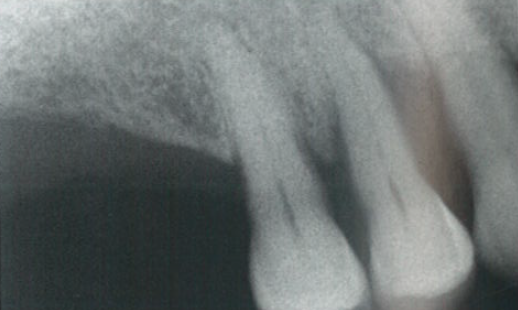

临床情况保持稳定约2年,从最初的治疗开始已经过了大约22年,在第一象限的同一区域发生了第三次复发(图5和图6),在复发期间,瘘管位于颊侧(图7)。根尖片(图8)显示插入光纤所示的瘘管的路径。之所以选择非手术治疗是因为患牙仍有牙髓活力,并且患者只有轻微不适,并无明显疼痛。

图6  牙周病复发后影像